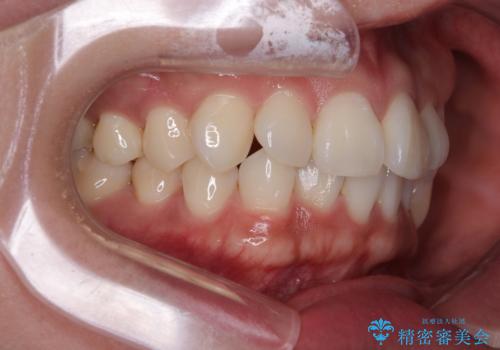

初診時、上下顎ともに歯列の不正が認められ、特に左下の小臼歯が大きく歯列から外れている状態でした。その影響により、下顎の正中が左側へシフトしており、見た目だけでなく噛み合わせにも影響が出ていました。

左下の小臼歯をきれいに歯列内へ並べるためには、まず十分なスペースの確保が必要でした。

そこで本症例では、上顎右側にアンカースクリュー(矯正用インプラント)を埋入し、そこからゴムかけ(顎間ゴム)を行うことで、下顎の正中を右方向へコントロール。

これにより、左下小臼歯がく並ぶためのスペースを確保することができました。